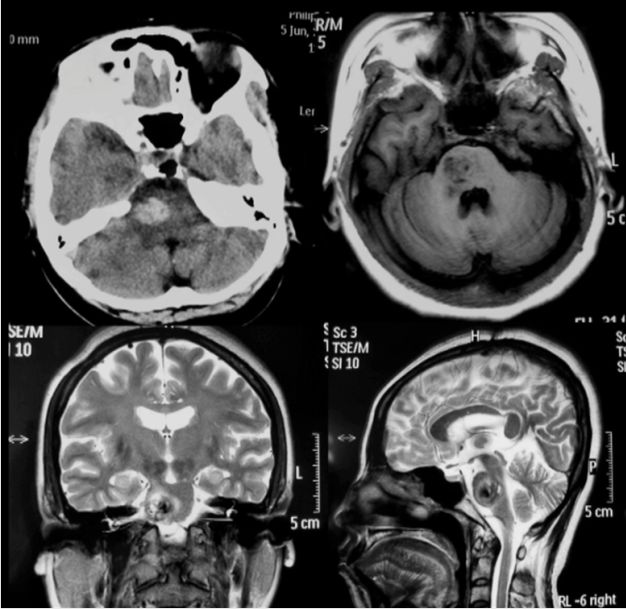

听神经瘤

手术体位个性化选择